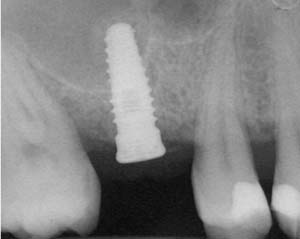

A 45-year-old female was referred for implant placement and prosthetic treatment in the area of tooth No. 24. The tooth had been extracted 4 years prior; the patient did not wear any denture thereafter. The radiograph revealed adequate bone height and a 5-mm to 6-mm ridge at the crest (Figure 2). It was decided to place a 11.5 mm in length, 3.75 mm in diameter Tapered Screw-Vent® implant (Zimmer Dental, www.zimmerdental.com) using the alveolar remodeling technique in the area of tooth No. 24.

Figure 2 Preoperative view of the area around tooth No. 24. On the left, a previously placed implant abutment

is visible.

Figure 4 Implant positioning; the radiograph taken 4 weeks after placement confirmed good primary stability.